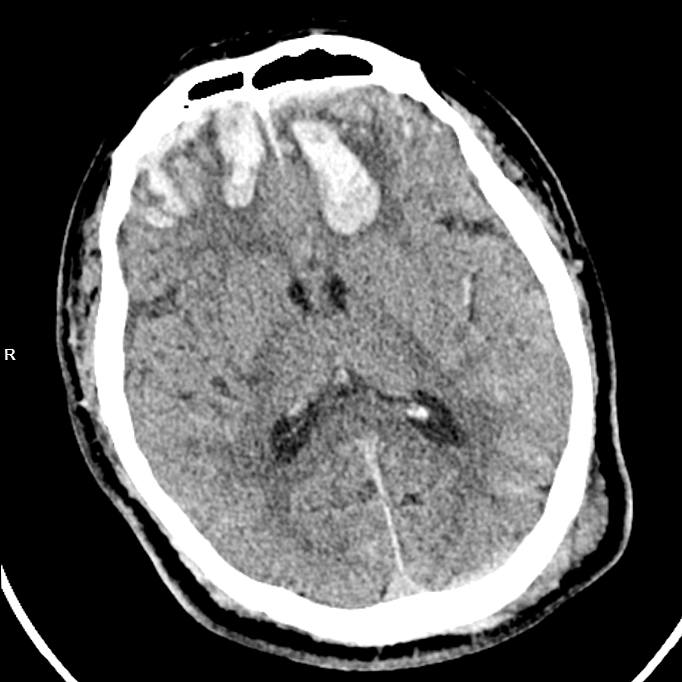

【严重脑挫裂伤】

胸外科医生率先出手,紧急置入胸腔闭式引流管,成功排出压迫肺部的血气胸,为呼吸功能争取喘息空间;神经外科团队紧盯颅内情况,精准用药控制脑挫裂伤引发的脑水肿,严防脑出血恶化;骨科团队则针对右侧肱骨骨折制定手术方案,为后续康复打下基础。

治疗期间,周朝阳副书记高度重视,每天都会出现在ICU,俯身查看李阿公的病情,从颅内血肿吸收情况到骨折愈合进度,从用药剂量到护理细节,每一项都逐一叮嘱、严格把关。

入院第37天,经过多学科团队的通力协作,阿公的颅内血肿基本吸收,骨折部位顺利愈合,呼吸功能恢复正常,各项生命体征平稳,终于达到转出ICU的标准。